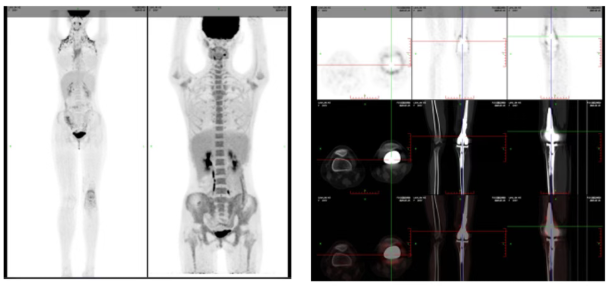

*PET-CT 影像检查图

近日,14岁女孩小赫(化名)在长春国文医院淋巴瘤血液病病区完成骨肉瘤治疗后,顺利重返校园。从确诊骨母细胞型骨肉瘤,到经历化疗、全膝关节置换术,再到成功度过严重并发症危险期,这名少年在医护团队全程守护下,从病房重新跑回了操场。

小赫确诊时肿瘤进展较快,科室未采用固定治疗模式,而是根据她的病情变化和身体耐受情况,动态调整治疗路径。每一次方案调整都紧扣肿瘤退缩情况,既严格遵循诊疗规范,又把“守护孩子未来”放在首位。科室协同骨科顺利完成左侧全膝关节置换术,术后病理提示脉管、神经均未累及,切缘无肿瘤残留,为孩子的长期生存和肢体功能恢复打下了坚实基础。